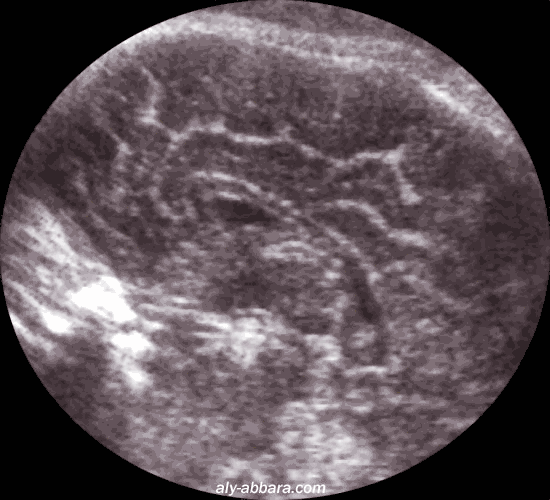

Coupe rasant la face interne d'une hémisphère du cerveau fœtal à 39 SA

on met en évidence une partie des circonvolutions du cortex cérébral

Comparer cet aspect à l'aspect du cortex cérébral dépourvu de circonvolutions à 26 SA